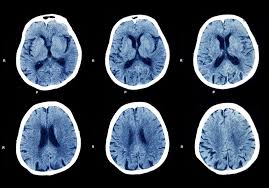

Wann wird MRT und wann CT gemacht. Die Computertomografie Computertomographie CT ist ein medizinisches Verfahren zur Darstellung von Körperstrukturen. Bei Blutungen oder Verletzungen des Kopfes ist die Computertomographie das Mittel der Wahl.

Bei der Schlaganfall - und Lungendiagnostik sowie bei bestimmten Tumoruntersuchungen um einige klassische Beispiele der CT- Anwendung zu nennen überwiegt ihr Nutzen meist um ein Vielfaches einen eventuellen theoretischen Strahlenschaden. Bei schweren Unfällen können mittels CT in kürzester Zeit innere Verletzungen Blutungen oder Knochenbrüche sichtbar gemacht machen. Ist der CT-Wert niedrig war viel Virus in der Probe.

Bei Kontrastmitteln wird beim MRT vorwiegend Gadolinium eingesetzt während beim CT vorwiegend jodhaltige Kontrastmittel zum Einsatz kommen. CT ist die Abkürzung für Computer-Tomographie. In diesem Artikel beschreiben wir Ihnen die Durchführung einer Untersuchung sowie verschiedene spezielle Einsatzgebiete dieser Technik. Die Computertomographie CT ist ein modernes Schnittbildverfahren durch das ein detaillierter Blick in den menschlichen Körper möglich wird. Mit modernen CT-Geräten geht das sekundenschnell und die diagnostische Aussagekraft ist extrem hoch. Die Untersuchung ist schnell durchführbar und sehr präzise. Wie bei einer normalen Röntgenuntersuchung kommen auch bei der CT-Untersuchung. Als CT bezeichnet man die sogenannte Computertomographie. Jedoch wird nicht nur ein Bild aufgenommen sondern eine Serie von Bildern während sich der.

Die Untersuchung ist schnell durchführbar und sehr präzise. Bei schweren Unfällen können mittels CT in kürzester Zeit innere Verletzungen Blutungen oder Knochenbrüche sichtbar gemacht machen. Der CT-Wert ist ein Maß für die Menge an Virus in einer Probe etwa im Rachen-Abstrich. In diesem Artikel beschreiben wir Ihnen die Durchführung einer Untersuchung sowie verschiedene spezielle Einsatzgebiete dieser Technik. Die Untersuchung ist schnell durchführbar und sehr präzise. Das ist ein Verfahren welches genau wie die klassische Röntgenuntersuchung mit Röntgenstrahlung arbeitet. Die Aufnahmen sind wesentlich detaillierter als herkömmliche Röntgenaufnahmen und erleichtern zum Beispiel die Tumorfindung.